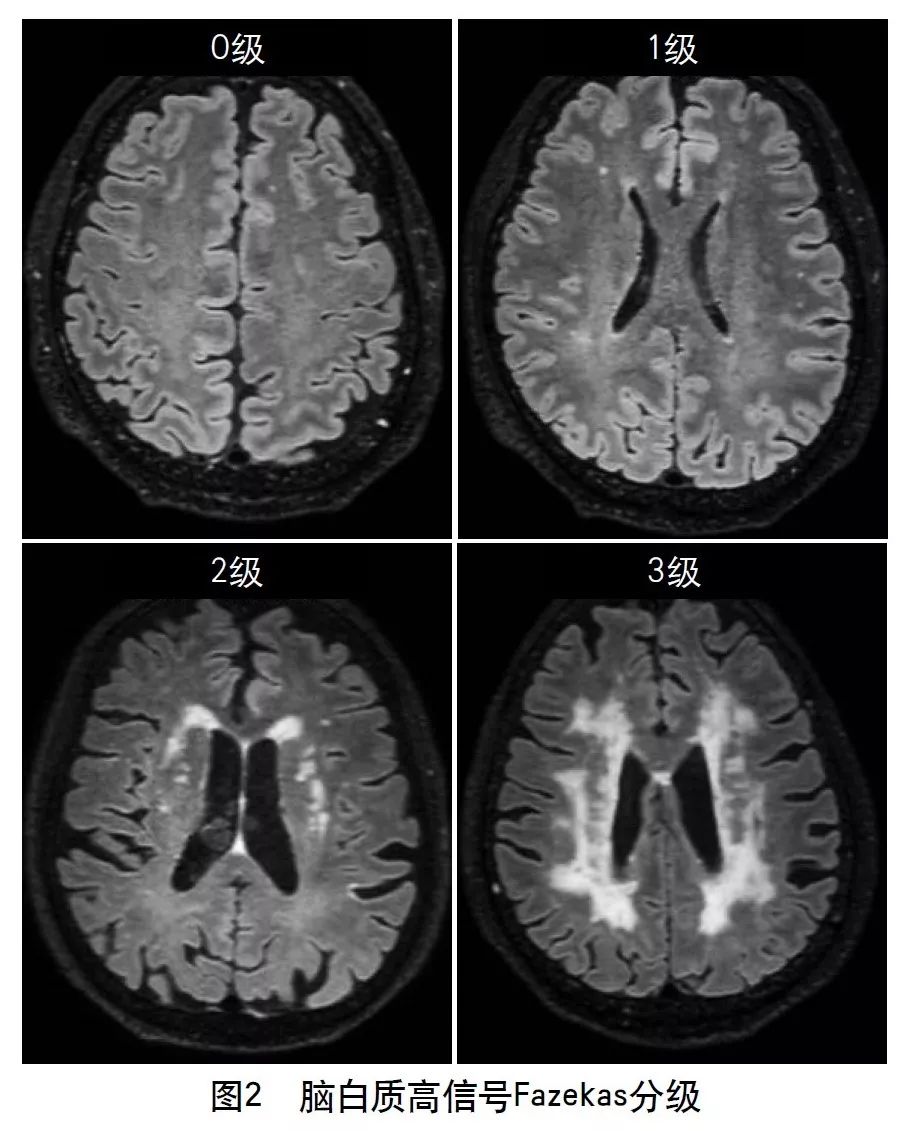

4.2.3 假定血管源性的白质高信号

假定血管源性的白质高信号定义为:脑白质异常信号,病变范围大小不等,在T2WI或FLAIR上表现为高信号,无腔隙,T1WI上呈等信号或低信号(不及脑脊液)。除非特别说明,皮质下灰质病变及脑干病变不属于白质高信号。假定血管源性的白质高信号的提出,排除了由其他非血管源性疾病所致的白质病变,如多发性硬化、白质营养不良等。

目前对脑白质高信号的影像学评价方法很多,主要有半定量和定量评估。半定量方法主要有Fazekas直观评分量表(图2)、年龄相关脑白质改变(ARWMC)量表、Scheltens量表。其中,Fazekas直观评分量表临床最常用,ARWMC量表可结合病变部位进行分析,能提供更多有效信息。定量方法包括Kropper法和FreeSurfer法,主要利用全自动定量分析软件对扫描后的头颅MRI图像进行分析,通过识别病变区异常信号、勾选病变区、计算病变体积来进行定量分级,从而定量评估白质病变的严重程度。